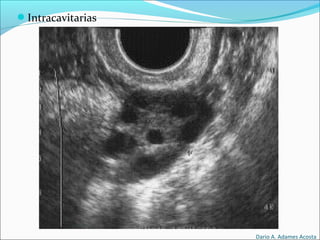

Tipos de Transductores

Intracavitarias

Pueden ser lineales

y/o convex.

Se usan para

exploraciones

intrarectales e

intravaginales.

Las frecuencias de

trabajo suelen ser

entre 5 y 7.5 MHz.